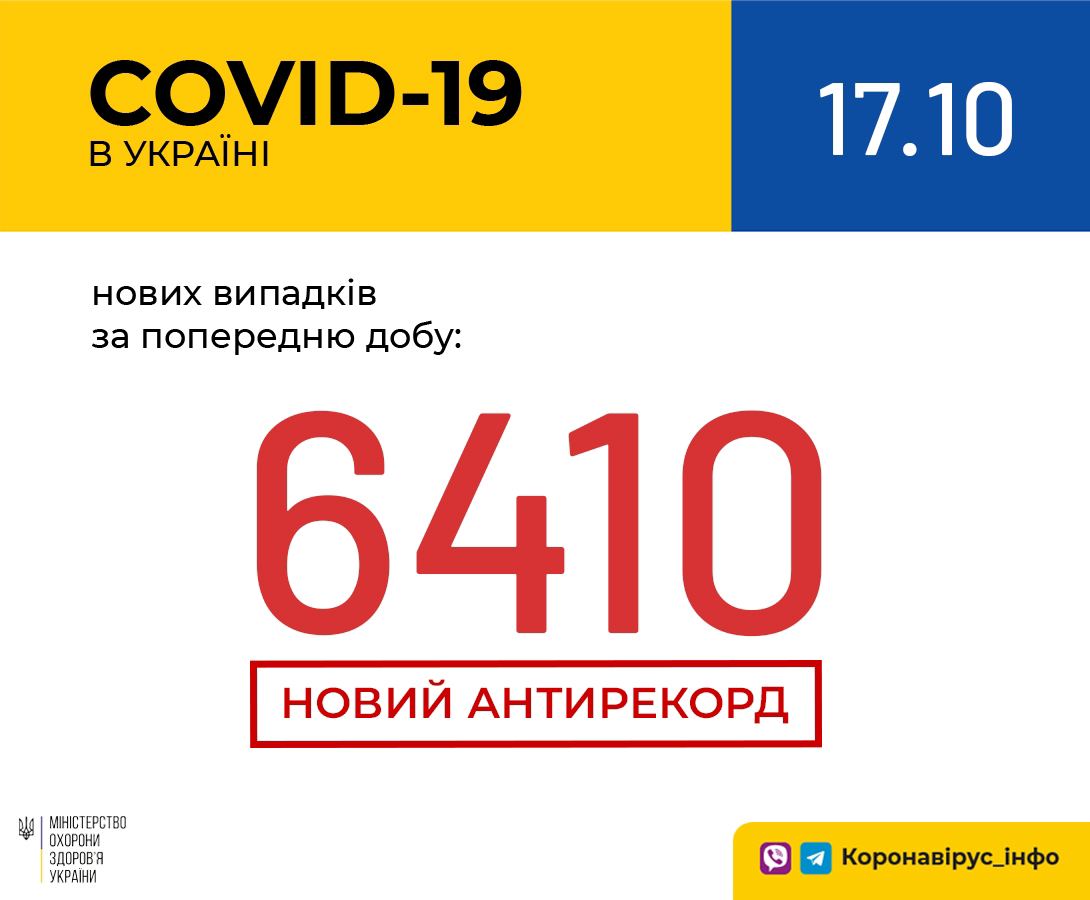

Більше 3 тисяч випадків захворювання на коронавірус зафіксували в Україні за добу

11.09.2020 09:37